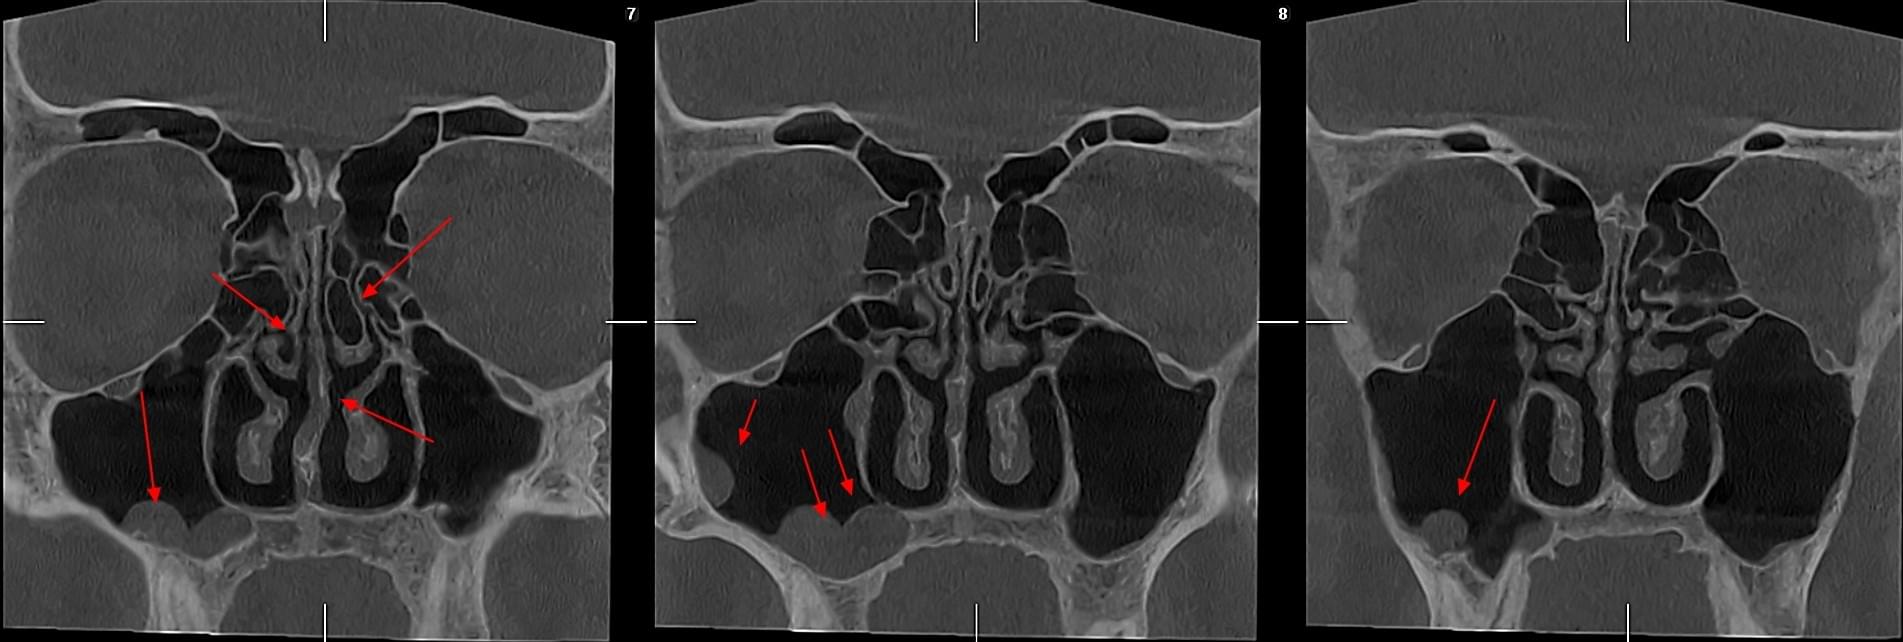

КПКТ (конусно-променева комп’ютерна томографія) — це 3D-знімок високої роздільної здатності. На відміну від звичайного рентгену, КТ показує:

У MyRayLab використовують сучасний апарат Planmeca 3D — доза опромінення всього 12 мкЗв (в 10–20 разів нижче, ніж у звичайних КТ), сканування 10 секунд, HD-якість.

Діагностика гайморових пазух за допомогою КТ

У сучасній медицині КТ придаткових пазух носа (або КТ синусів) — це «золотий стандарт»

діагностики для ЛОР-лікарів та щелепно-лицевих хірургів. Звичайний рентген часто не

показує повну картину, а МРТ не завжди доступний і дорожчий. Комп’ютерна томографія дає

детальну 3D-модель усіх пазух (гайморових, лобних, клиновидних та решітчастого

лабіринту) за 10 секунд і з мінімальною дозою опромінення.